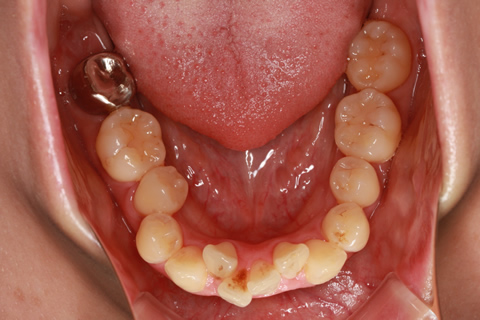

ハーフリンガル矯正3:上の歯のみ舌側矯正で治療(矯正期間24ヶ月)

治療前

治療中(開始直後)

治療中(開始半年後)

治療後

- 年齢・性別

- 25歳女性

- 治療期間

- 2年0ヶ月

- 抜歯

- 上下4番抜歯

- 治療費

- 110万円

- 治療内容

- 施術の副作用(リスク)

- 表側矯正と比較して、力学的な操作性が複雑なため、ボーイングエフェクトを起こしやすい。